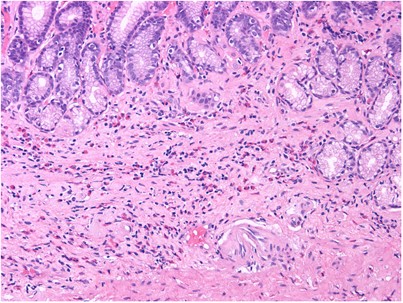

The histological findings in gastric biopsies of study patients are summarized in Table 4. The median eosinophil density was 539/mm2; mean±SD=653±418/mm2; range 127–2108. Figure 1 shows an antral biopsy with markedly increased eosinophils. All patients had eosinophilic clusters scattered in the lamina propria. Sheets of eosinophils (Figure 2) were seen in the biopsies from 38 (63.3%) patients. The gastric epithelium was infiltrated by eosinophils in 53 (88.3%) patients (Figure 3); the epithelial involvement was scored as abundant in 19 cases and rare in 34. In contrast to neutrophilic processes (eg, as in H. pylori infection), eosinophils tended to surround the foveolae and infiltrate their epithelium, but virtually never spilled into the lumen to form eosinophilic ‘pit abscesses’ (Figure 4). Muscularis mucosae or submucosal tissue involvement was noted in 27 patients (Figure 5). Intestinal metaplasia was seen in the biopsies of two patients. H. pylori organisms were not detected by immunohistochemistry in any of the patients.

Figures 6a and b illustrate the eosinophilic content typically found in the antrum and corpus of control subjects. The mean eosinophil count for the 135 control patients (84 women, or 62.2%; median age 50 years, range 4–81) was 15.5±16.8 SD eosinophils/mm2 (range 0–110). Only one of the controls (a 56-year-old woman of Japanese origin) had a mean count of 110 eosinophils/mm2. All other controls averaged fewer than 55 eosinophils/mm2. There were no significant differences between the counts in biopsies from the antrum and corpus, and no significant variation by either age or geographic location (data not shown). The median density of eosinophils in age- and sex-matched patients with H. pylori infection or Crohn's disease was lower than in normal controls (15.8 and 9.5 eosinophils/mm2, respectively, vs 25 eosinophils/mm2 in subjects with a normal stomach). However, both mean density and standard deviation were higher, reflecting the presence of a few patients with elevated counts (up to 203–219 eosinophils/mm2) in each of these two groups.